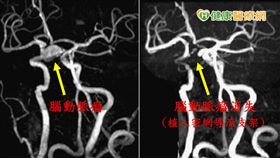

2/3腦動脈瘤破裂非死即殘!

腦動脈瘤俗稱腦血管瘤,有如「腦中不定時炸彈」,一旦破...